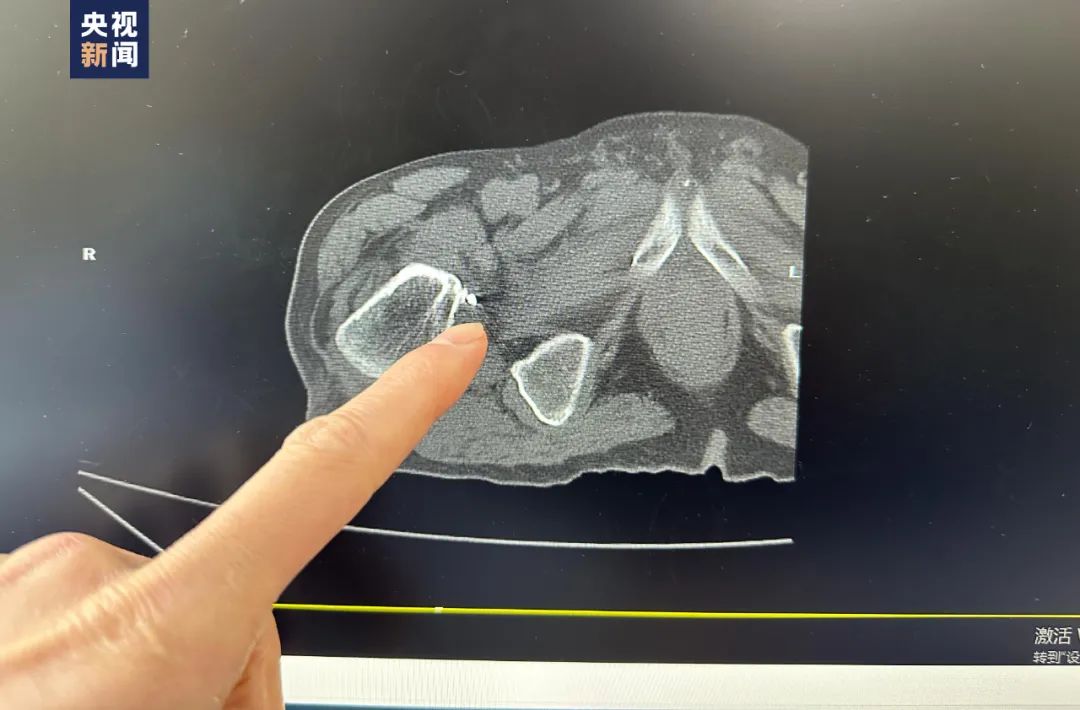

檢查時(shí)意外發(fā)現(xiàn)髖關(guān)節(jié)處

有戰(zhàn)爭(zhēng)時(shí)期殘留的多塊彈片

這些彈片位于髖關(guān)節(jié)的內(nèi)側(cè)緣

距體表有十幾厘米深